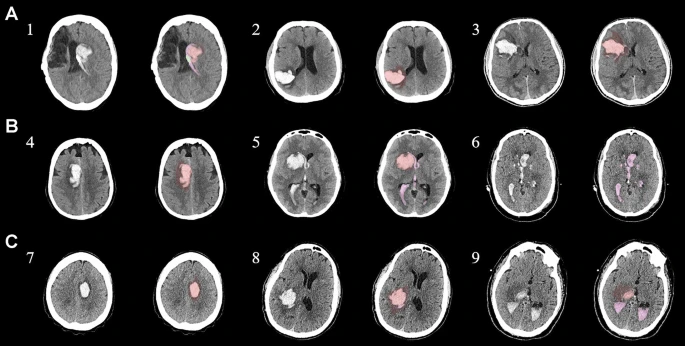

本研究納入2018年1月1日至2020年10月31日發病168小時內發生急性ICH的患者。間充質干細胞被靜脈注射給9名患者(5名女性,4名男性),平均年齡(范圍)為61(36-84)歲。表1總結了人口統計學和臨床??特征 。出于描述目的,患者按照入組順序獲得編號,并連續分配到三組中的一組,每組三人。根據模型 2 分割,ICH體積范圍為0.1至54.9mL(平均ICH體積為23.5mL)。5例ICH累及局部腦葉,其余則位于基底節或外囊深處。在三名患者中,ICH位于丘腦(圖1),在一名患者中,血腫位于多個腦結構(即尾狀核、殼核和蒼白球)。平均而言,MSC在ICH后3天進行注射。

具有臨床特征的探索性成像體積模型分析

ABC/2模型1和模型2分割方法通過ICH和IVH體積的線性回歸顯示出良好的相關性(圖3a、b)。與模型2分割體積方法(例如,每個CT15-20分鐘)相比,模型1ABC/2派生的半定量方法和改進的Graeb IVH方法完成時間較短(例如,2-5分鐘)。有趣的是,NIHSS評分與IVH體積M2方法的比較顯示出線性相關性(R 2 ?= 0.7217),并且當IVH小于20mL或大于20mL時,NIHSS評分似乎出現聚類(圖3c)。PHE分析顯示MSC注射劑量和PHE體積之間存在輕微的負相關關系。

a,通過模型1ABC/2派生方法與vol模型 2(分割)進行的神經影像ICH vol的線性回歸。b、IVH通過模型1和定量分割模型2方法對Graeb進行了修改。c,出血量和NIHSS評分與IVH量通過分割進行比較。